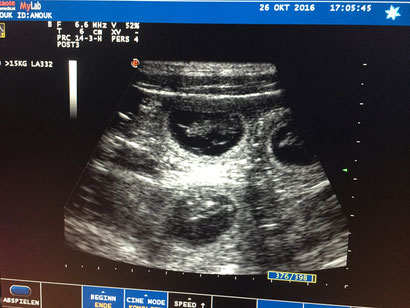

Ultraschall vom 26.10.2016, es sind mindestens vier kleine Welpen gesichtet worden.